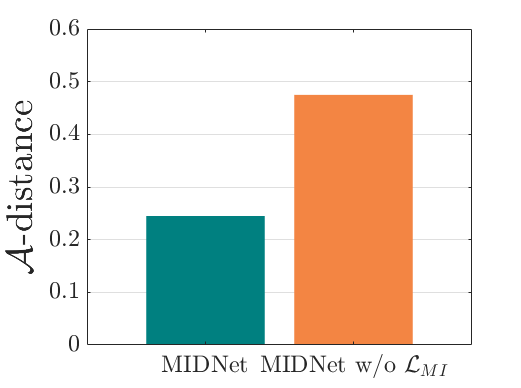

The classification performance of baselines and the proposed model are shown in Table. III. We observe that MIDNet outperforms the state-of-the-art on on the most important test data for average F1-score and recall. Among all the models in the ablation study, MIDNet+ achieves the best performance on and , demonstrating that metric learning contributes to the separation of seen categories in both domains. MIDNet outperforms MIDNet w/o , MIDNet w/o and MIDNet w/o on , illustrating the importance of all proposed components in MIDNet for the classification of unseen categories in the target domain. In addition, Fig. 7 (b) shows the effectiveness of mutual information disentanglement () to learn domain-invariant categorical features.